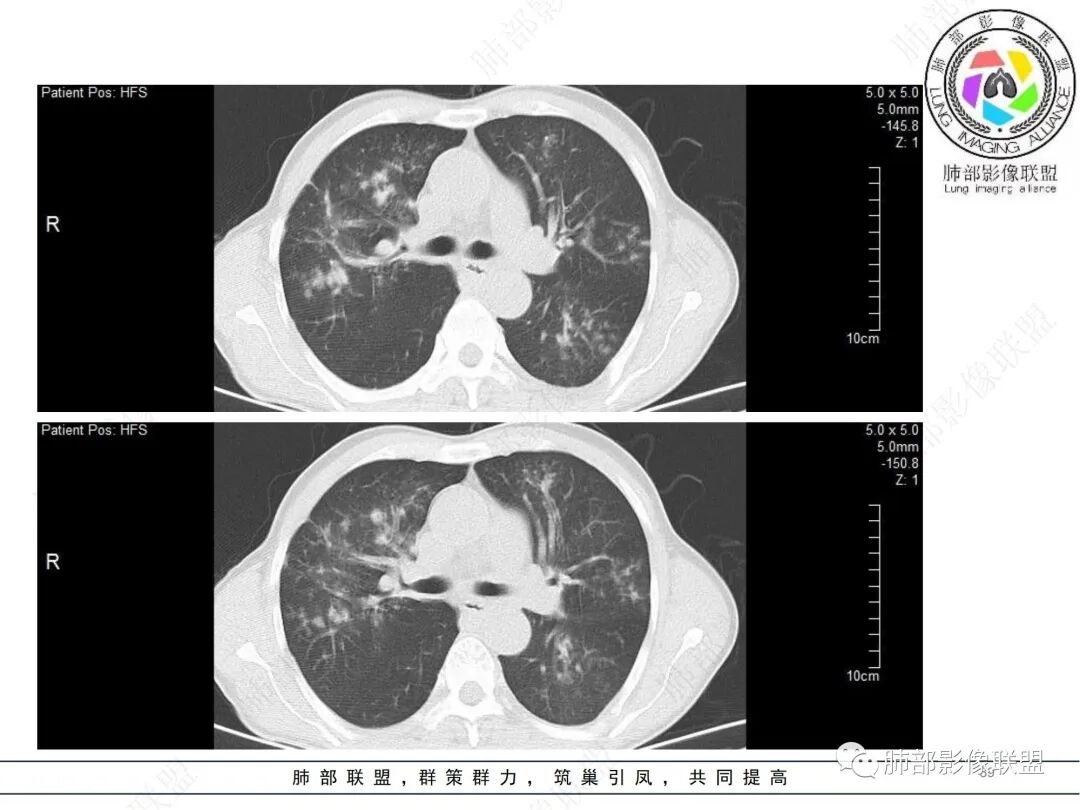

58岁男性,咳嗽胸闷3天,咳较多褐粘液痰,无发热。有2型糖尿病病史。白细胞与中性粒细胞升高。CRP升高。鳞状上皮细胞癌抗原轻度升高。结核T细胞免疫斑点实性阳性。肺炎支原体、衣原体IgG轻度升高。支气管镜显示支气管炎性改变、右肺下叶背段管腔狭窄。2.影像特点:

2022.6.24CT显示两肺弥漫性段、亚段支气管壁增厚(两肺各叶都累及),增厚的支气管壁外可见沿着支气管分布的渗出、实变影。另外远端肺内亦可见多发树芽影、结节影,其边界欠清晰。右肺下叶基底段局部胸膜下亦可见小斑片影,边界不清。2022.6.27CT显示两肺增厚的支气管壁外的渗出实变影明显增多、范围更广。远端肺内病灶亦增多、范围增大。部分位于胸膜下的病灶可见侧向融合趋势。3.病例分析:

中老年男性,咳嗽咳痰胸闷3天就诊,急性过程。有糖尿病基础。实验室检查炎症指标明显升高。结合影像学气道密切相关,首先考虑感染性病变。

就临床而言,患者起病急,实验室炎性指标升高明显,结合宿主因素等,会将细菌感染纳入鉴别诊断范围。

影像学病灶双肺分布,支气管广泛增厚,较少见于普通社区肺炎,而更多见于气道侵袭性曲霉病。病原学检查证实烟曲霉感染的存在。